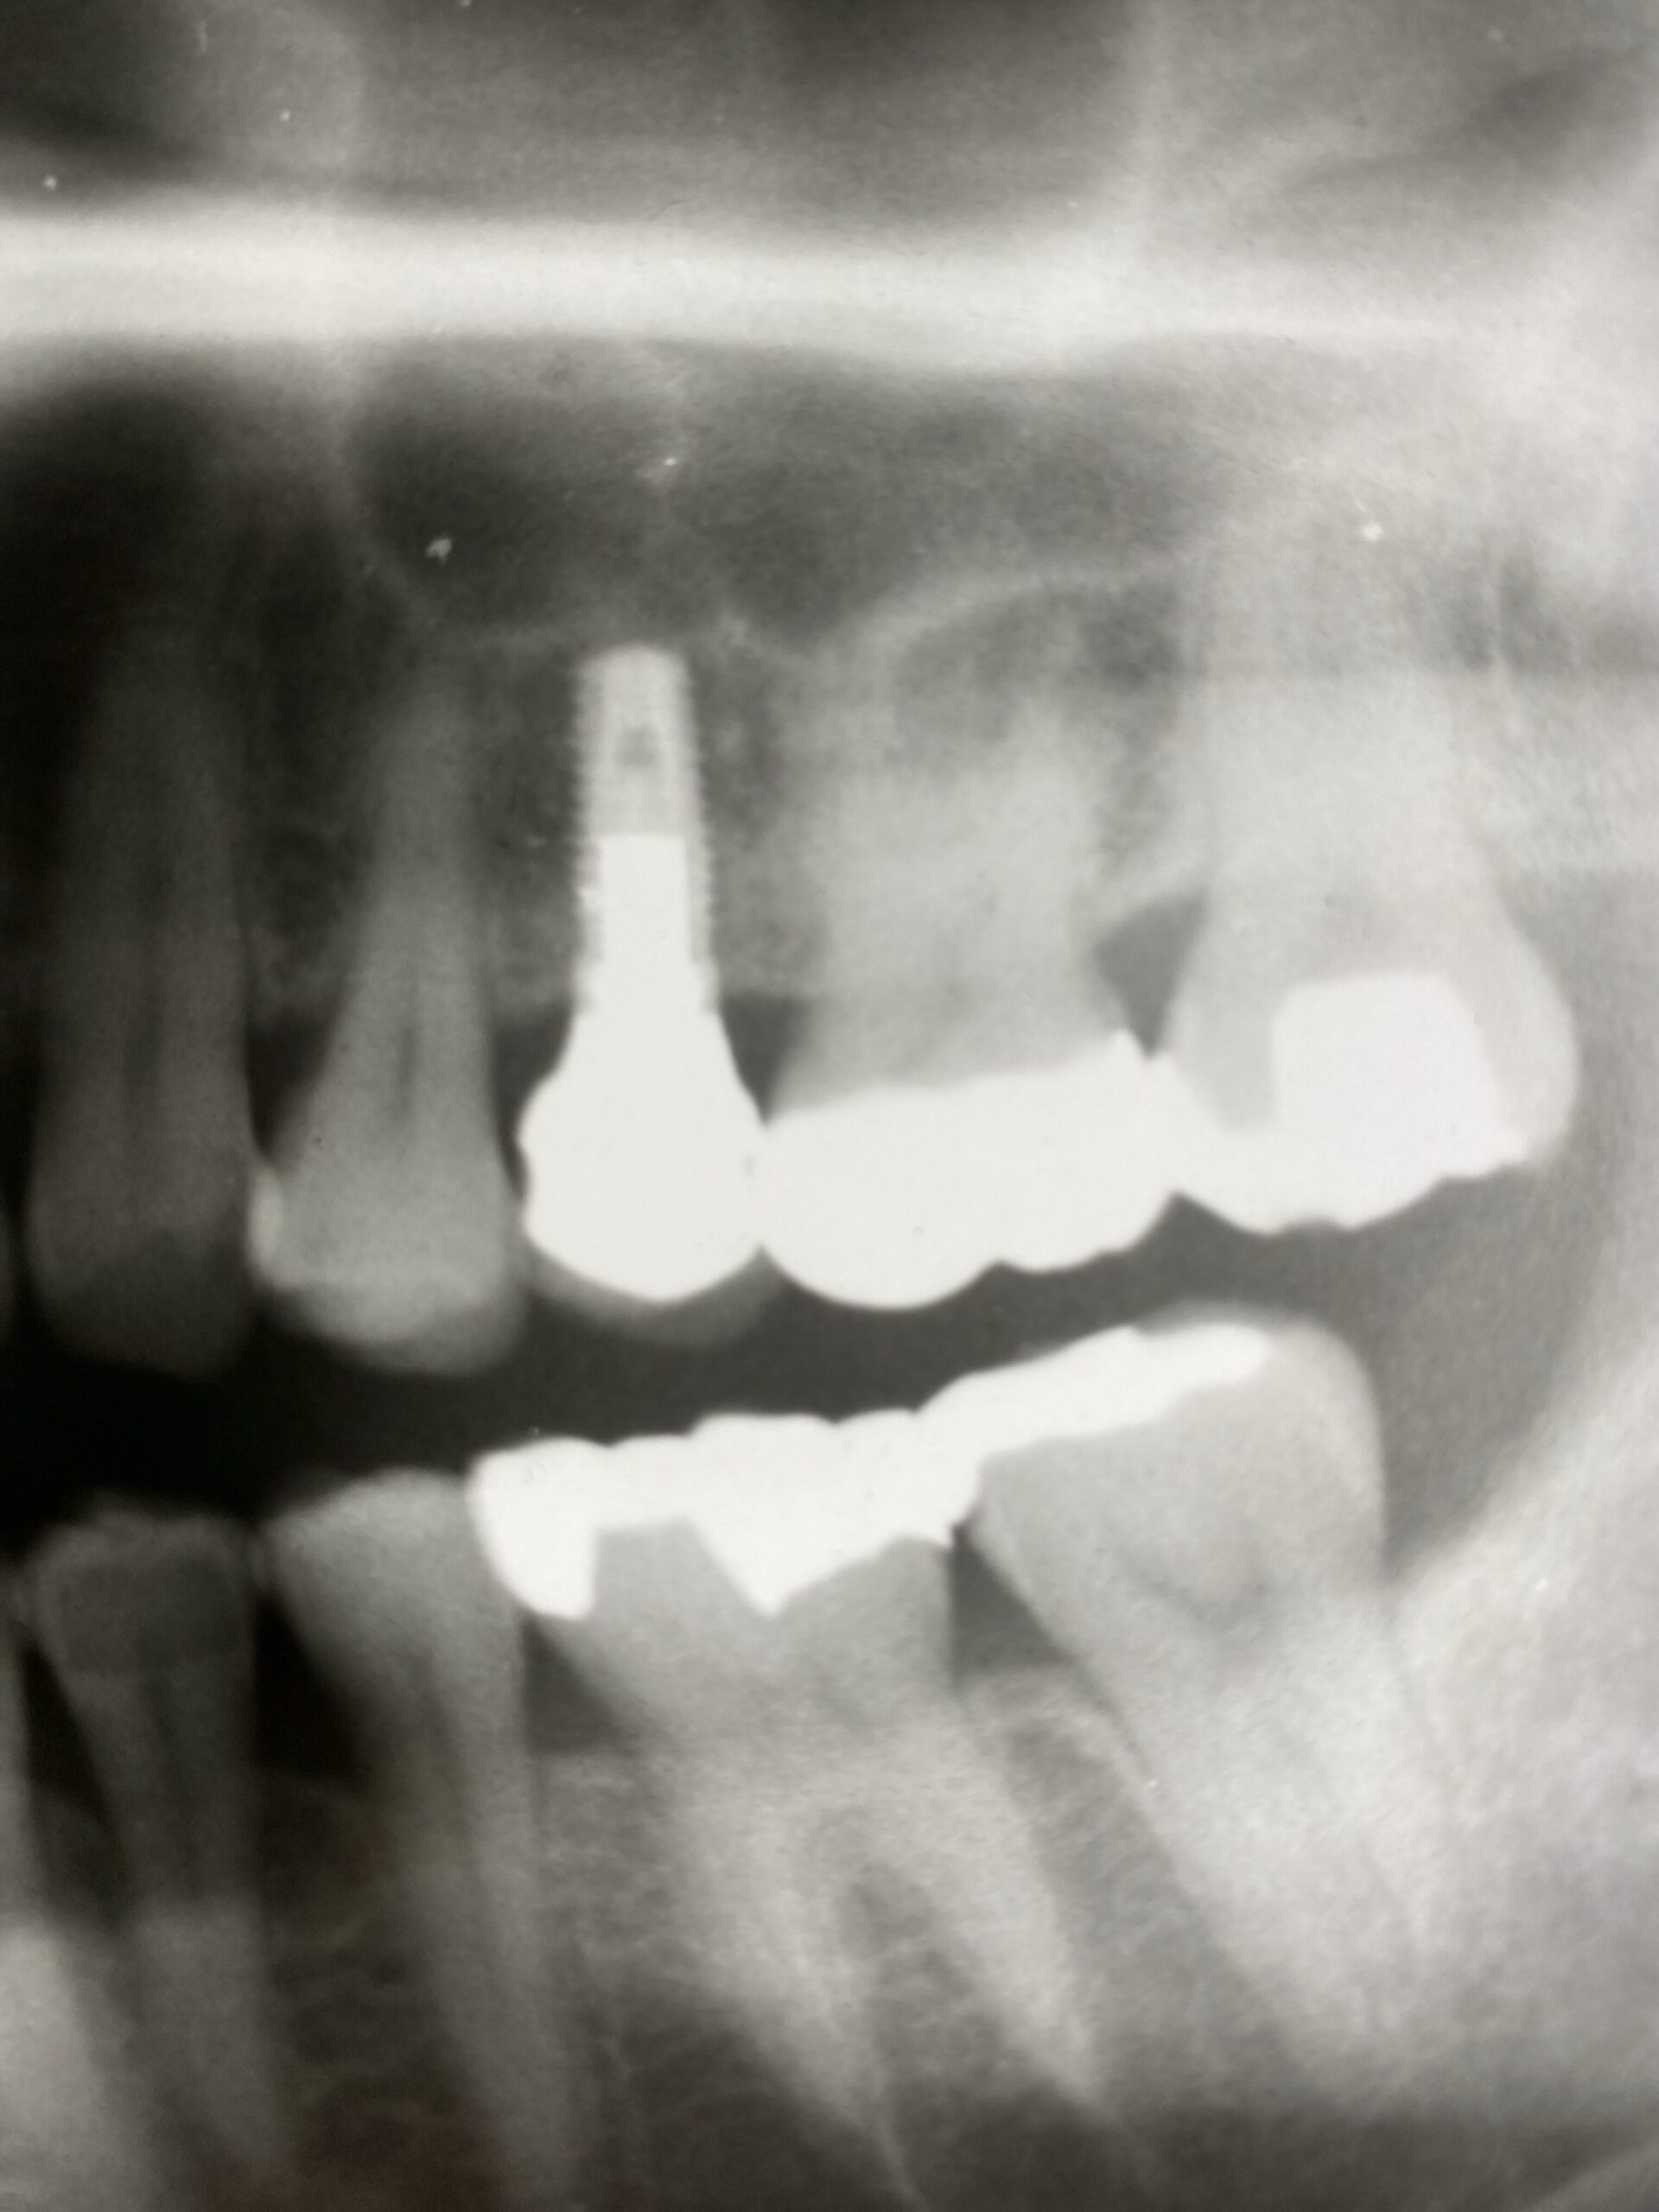

インプラントの長期予後について

- 平均的な寿命: インプラントの10~15年の生存率は、上顎で約92-93%程度、下顎で94-96%程度とされています。